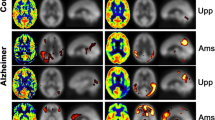

Figure 1 shows sections of T1-weighted anatomical images averaged over all HC with areas of lower CBFcorr in patients as revealed by the ANOVA analysis overlaid in yellow (P < 0.001 uncorrected) and red (P < 0.05, FWE corrected). Table 2 summarizes anatomic regions, cluster sizes, z values and MNI coordinates of peak locations. Lower CBFcorr in patients with MCI as compared to HC was found in the right and left superior parietal gyrus, the right and left angular gyrus, the left inferior parietal gyrus, the left and right middle temporal gyrus and the middle occipital gyrus. Only the differences in the right angular gyrus and in the left superior parietal lobe survived FWE correction for multiple comparisons. Patients with AD showed lower CBFcorr than HC in the right angular gyrus, in the left and right superior parietal gyrus, in the left and right inferior parietal lobe, in the right middle occipital gyrus, in left precuneus and caudate. The differences in CBFcorr attained statistical significance on an FWE-corrected level in the left superior parietal lobe, in the right angular gyrus, in the middle occipital lobe and in the left precuneus. There was only a small cluster in the middle cingulate where patients with MCI exhibited higher perfusion than patients with AD. No regions of hyperfusion were detected in patients with AD and MCI compared with HC according to the ANOVA analysis.